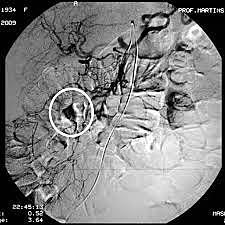

Egas Moniz realiza la primera angiografía